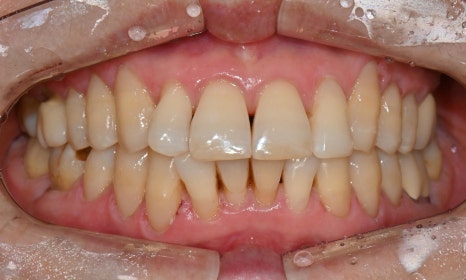

본 환자는 70세 여환으로 가만히 입을 다물고 있을 때 화난 것 처럼 보인다고 해서 튀어나온 앞니를 조금 넣고 싶다는 주소로 내원하셨습니다. 전체적인 치아 및 잇몸 상태를 검진해본 결과, 마모되어 깨진 치아도 있었고, 치경부(치아와 잇몸 사이 경계 부위)가 마모되어 파여 있는 부위도 많았습니다.

2025.2.3. 초진